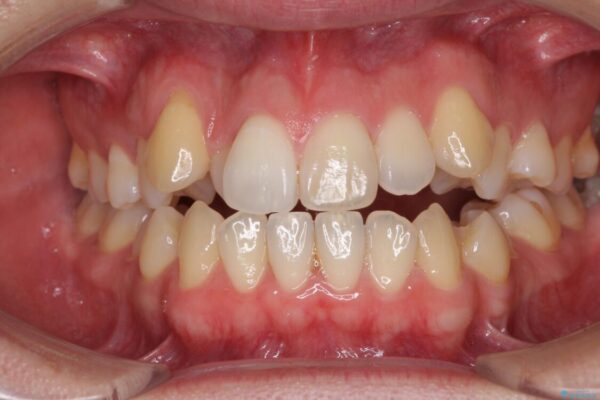

治療後

• 左右の八重歯が気になる ワイヤー装置での咬み合わせ改善 治療後画像

八重歯と前歯のデコボコを気にして来院された患者様です。

舌の突出癖がなかなか改善されず、上下前歯部の接触が得られるまでに予定の倍ほどの期間がかかりました。